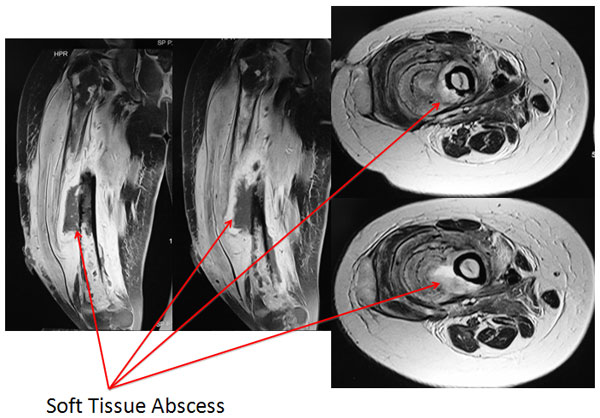

| MRI |

| The MRI showed a significant amount of infection in the soft tissues on the poster-lateral aspect along with the marrow infection. |